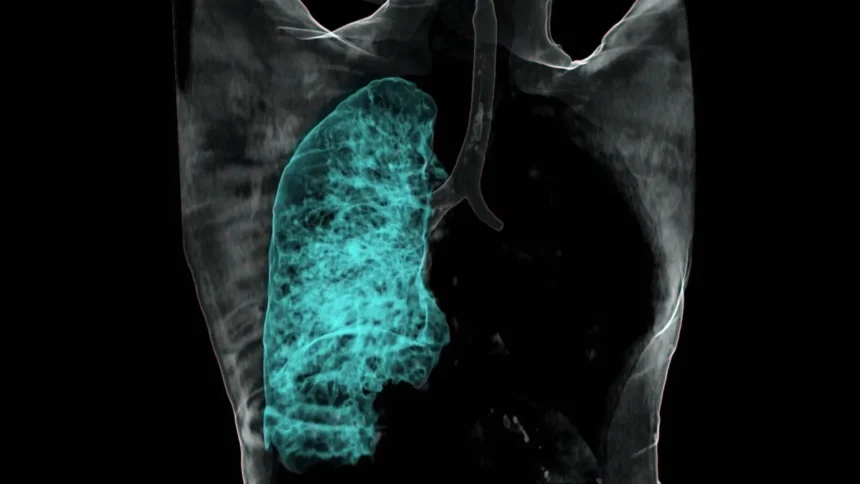

A Nemzeti Rákregiszter frissen közzétett adatai szerint 2025 első negyedévében a tüdőrák diagnózisok száma 5%-kal csökkent az előző év azonos időszakához képest. Ez az első jelentősebb visszaesés az elmúlt évtizedben. Dr. Kovács Erzsébet onkológus főorvos szerint ez részben a dohányzás visszaszorulásának és a korai szűrőprogramok hatékonyabbá válásának köszönhető.

A statisztikák ugyanakkor továbbra is aggodalomra adnak okot: Magyarország még mindig Európa élmezőnyében szerepel a tüdőrák előfordulási gyakoriságát tekintve. Évente közel 8200 új esetet diagnosztizálnak, és mintegy 6500 honfitársunk veszti életét a betegség következtében. A férfiak körében valamivel gyakoribb (58%), de az elmúlt években a női megbetegedések aránya folyamatosan növekszik.

Az Országos Onkológiai Intézet elemzése szerint a regionális eltérések is jelentősek. Míg az észak-magyarországi régióban 100 ezer lakosra vetítve 89 új eset jut évente, addig a nyugat-dunántúli területeken ez a szám csak 62. Szakértők szerint ez összefügg az ipari szennyezettség mértékével és a dohányzási szokások területi különbségeivel.

Biztató fejlemény, hogy az ötéves túlélési ráta a 2020-as 18%-ról 2025-re 23%-ra emelkedett. „A célzott terápiák és az immunonkológiai kezelések robbanásszerű fejlődése mára kézzelfogható eredményeket mutat a túlélési statisztikákban is” – nyilatkozta Dr. Szabó János, a Pulmonológiai Klinika vezető onkológusa.

Az egészségügyi kormányzat tervei szerint 2025 második felében országszerte bővül a tüdőszűrő programok köre, különös tekintettel a magas kockázatú csoportokra. A szakemberek szerint a korai felismerés kulcsfontosságú, hiszen az I. stádiumban felfedezett tüdőrák esetén a gyógyulási esély akár 70-80% is lehet, szemben az előrehaladott állapotban diagnosztizált esetekkel.

A szakértők hangsúlyozzák: a megelőzés továbbra is a leghatékonyabb fegyver. A dohányzás elhagyása, a rendszeres testmozgás és az egészséges táplálkozás mind hozzájárulnak a tüdőrák kockázatának csökkentéséhez. Az új kezelési módszerek pedig reményt adnak azoknak is, akik már szembesültek a diagnózissal.